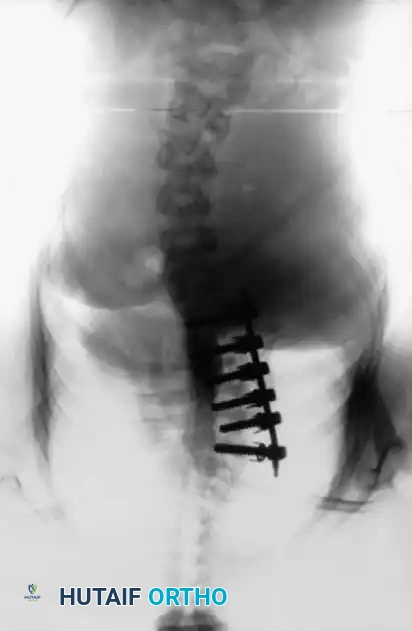

ANTERIOR INSTRUMENTATION FOR IDIOPATHIC SCOLIOSIS

Anterior instrumentation and fusion have historically been a well-accepted, powerful procedure for specific curve patterns, particularly thoracolumbar and lumbar curves.

THE POSTERIOR ALTERNATIVE: PEDICLE SCREW FIXATION

Given the morbidities associated with anterior surgery, many key opinion leaders have transitioned to all-posterior approaches. Shufflebarger et al. strongly advocated for a posterior approach utilizing pedicle screw fixation and posterior column shortening for lumbar and thoracolumbar scoliosis.

The Posterior Shortening Technique

Following a wide posterior release (including complete facetectomies and removal of the ligamentum flavum), the spine is instrumented with pedicle screws and a 5.0-mm or 5.5-mm rod system.

* Advantages: This technique allows the surgeon to fuse the exact same number of levels as an anterior approach while entirely avoiding the morbidity of thoracotomy or retroperitoneal dissection.

* Outcomes: It provides excellent, rigid correction of both coronal and sagittal deformities, allowing for the restoration of physiological lumbar lordosis through posterior compression.